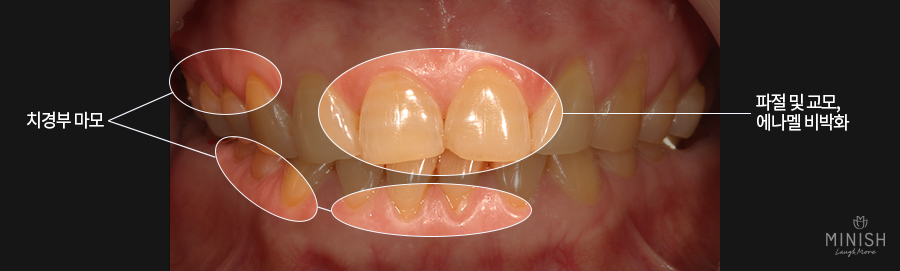

천안엄마는 치아노화의 대표적인 증상인 치아가 패이는 증상(마모)이 상당히 많이 진행되어 치아 속 상아질이 노렇게 드러나 있었으며 에나멜이 약해진 상태였습니다. 또한 어금니깨짐 즉, 파절로 인해 음식을 제대로 씹을 수 없었고 극심한 이시림 증상을 가지고 있었죠.

● 질환: 어금니깨짐, 치아 닳음(교모), 치아 패임(마모), 전체적인 에나멜 비박화

본론으로 돌아와서, 위 사진에서도 보실 수 있듯이 천안엄마의 치아 역시 많이 닳아 있는 상태(교모)였으며 치아가 패여서 상아질이 드러나는 치아 마모와 구치부가 깨지는 등 노화의 대표적인 증상들을 겪고 있었습니다.